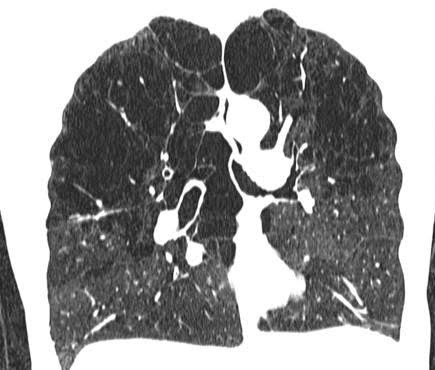

Centrilobular emphysema, or centriacinar emphysema, is a long-term, progressive lung disease. It's considered to be a form of chronic obstructive pulmonary disease (COPD). Centrilobular emphysema primarily affects the upper lobes of the lungs. It's characterized by damage to your respiratory passageways.